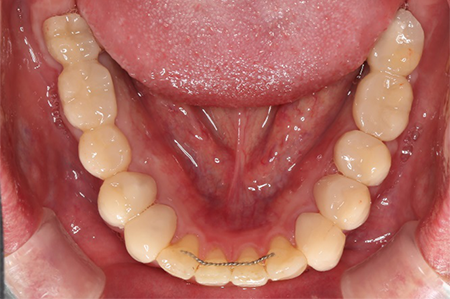

下の口腔内写真は初診時と矯正治療+補綴治療後のものになります。

この患者様は長い事歯科医院には通っておらず、下の歯は前歯以外は全て崩壊していることが分かります。

前から見ても歯が欠けてしまい、歯茎も赤く腫れてしまっているのが分かります。

一般的には入れ歯が妥当かと思われますが、患者様は33歳、まだまだ人生は長いです。

奥歯がないと前歯でしか噛めなくなってしまい、残っている前歯もいずれダメになってしまいます。

また、奥歯がなくなってからの期間が長かったため、入れ歯が入るスペースが奥にないのが分かります。

様々なことを鑑み、患者様とも何度も話し合いを行い、下の奥歯には必要最低限のインプラントを、他の歯も外科処置を施しなるべく歯を抜かない方法を取りました。

最終的に抜歯した本数は下の歯5本。上の歯に関しては全て残すことが出来ました。

奥歯があることで前歯の負担を減らし、前歯を失うリスクを下げることが出来ます。